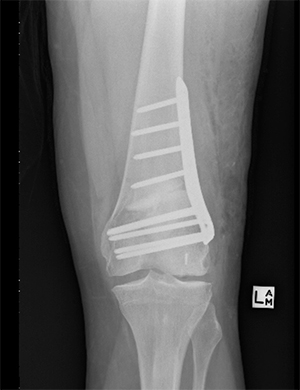

In the knee realignment procedure, the bone is cut 80% of the way across and then bent by a predetermined amount and fixed in place with a metal plate and screws. Sometimes bone is used to fill in the gap created by cutting and bending the bone.

In patients who are bow legged the tibia is normally cut just below the knee (High Tibial Osteotomy).

In patients who are knock kneed the femur is normally cut just above the knee (Distal femoral Osteotomy)